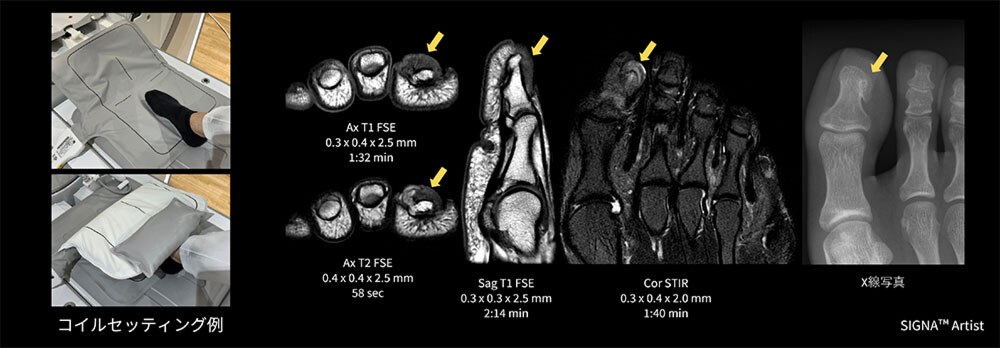

Case5 足部腫瘤造影検査

20代の男性。5年ほど前に海外で足部の手術を行っており、同足部の腫脹と痛みを訴えMRI検査を実施。足底部の強い痛みがあり、歩行困難かつ圧着困難のため、足部の荷重を和らげた体位にてMP Coilを挟む様にポジショニングを行い検査を施行。

右第1,2中足骨間に腫瘤を認め、周囲筋肉や腱を押し広げ、骨の間を通ってダンベル状に発育しており、第1中足骨に一部浸潤あり、境界明瞭で周囲骨の信号変化乏しい。肉腫やデスモイド、孤立性線維性腫瘍(SFT)などが鑑別に挙げられた(図7)。

患者さんの痛みが強くポジショニングが限定される中、負担が少ない体位でコイルを挟むだけで簡単に検査が行うことができ診断に貢献できた一例。

図7 足部腫瘤造影検査におけるMP Coilのセッティング例と臨床画像